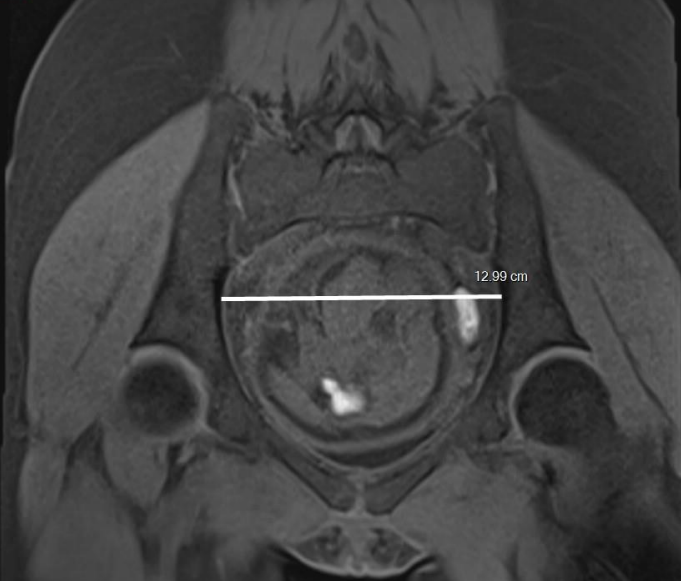

- Plan coronal oblique reliant la symphyse au promontoire et permettant de mesurer le diamètre transverse du pelvis.

- Enfin sur la coupe coronale oblique joignant la symphyse au promontoire, le diamètre transverse du pelvis, le plus grand diamètre transverse du pelvis.